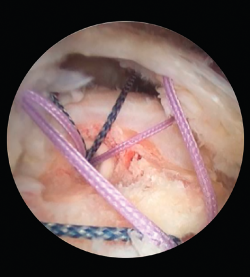

¿El resto de los procedimientos planteados son eficientes? El objetivo es obtener un hombro indoloro para una buena rehabilitación, con lo que la fisioterapia posterior al procedimiento quirúrgico tendrá un papel fundamental en la capacidad de recuperación del hombro (Figura 3).

Figura 3. Revisión de una rotura de manguito rotador.